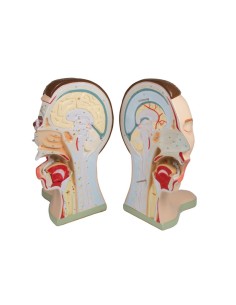

Découvrez le monde de l'anatomie avec des modèles anatomiques de précision

Bienvenue sur Tuttoanatomia.it, le portail de référence en Italie pour l'achat de modèles anatomiques, de posters, de lits portables, de simulateurs médicaux et de littérature spécialisée. Grâce à nos modèles anatomiques de pointe de 3B Scientific et Erler Zimmer, nous offrons une expérience d'apprentissage inégalée.

Des modèles anatomiques détaillés pour tous les besoins

Du crâne en 22 parties à verrouillage magnétique aux modèles de colonne vertébrale, des modèles d'articulation aux modèles de cœur, chaque pièce de notre collection est conçue pour une immersion totale dans l'étude de l'anatomie humaine. Nos modèles, réalisés à partir de scans d'os réels, garantissent une expérience tactile authentique et une fidélité de poids presque identique aux originaux.

Indispensables aux étudiants comme aux professionnels, nos modèles anatomiques sont des outils pédagogiques qui permettent d'observer les structures anatomiques avec précision, en évitant les dissections ou les études invasives. Ils sont également utiles pour expliquer les pathologies aux patients, ce qui rend la communication plus efficace et permet de gagner un temps précieux.